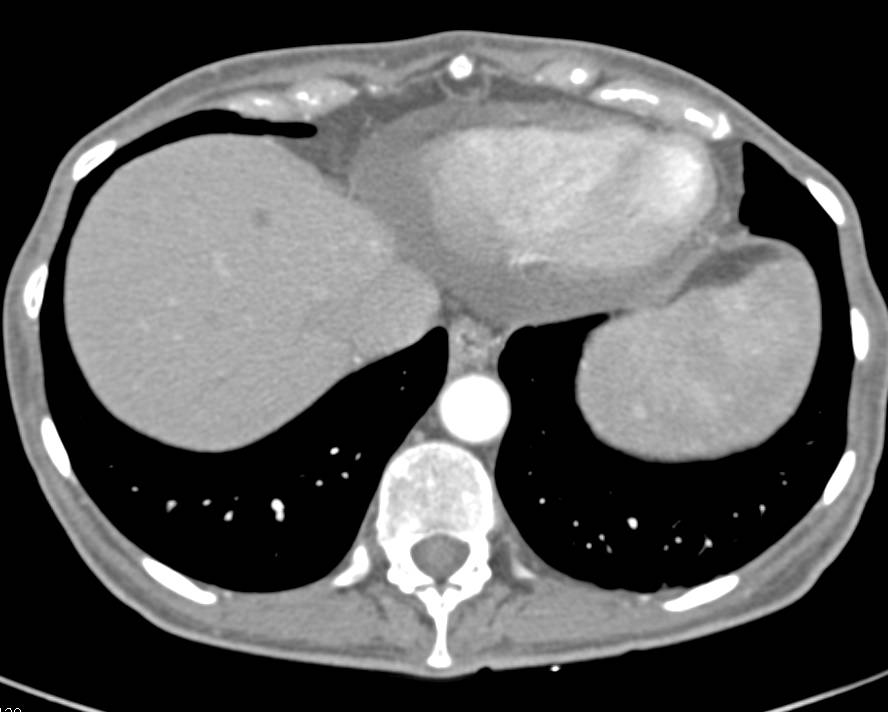

Subcapsular Hematoma in the Spleen